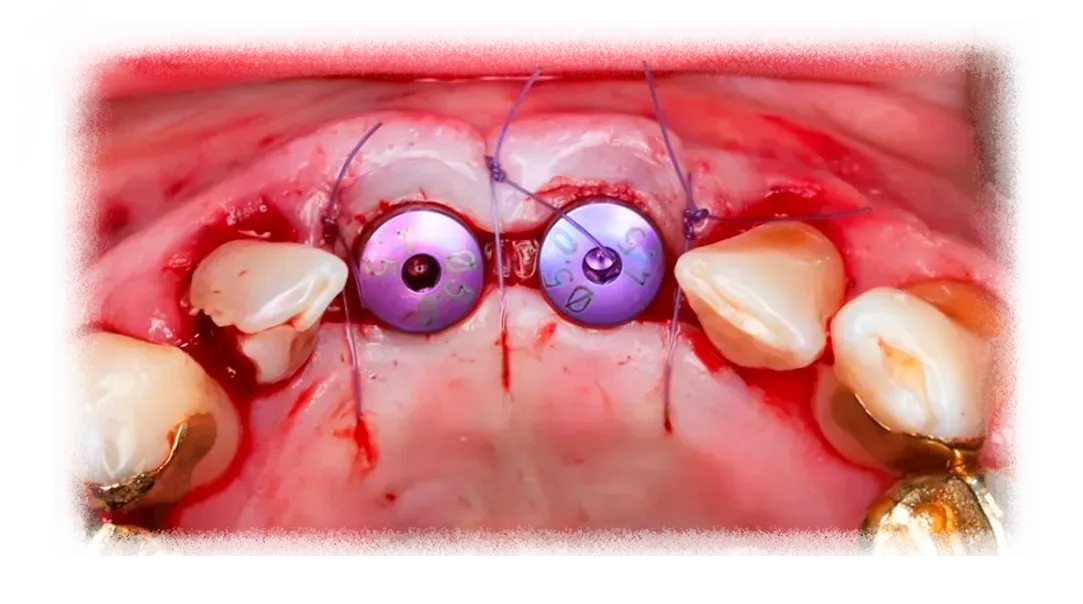

Successful regeneration depends on the interaction between biology, surgical technique, and biomaterial selection.

Key factors include maintaining space for bone formation, stabilizing graft materials, protecting the regenerative environment with appropriate membranes, and achieving stable soft tissue closure.

This program reviews these elements in detail so clinicians can approach GBR procedures with greater clarity in both planning and execution.